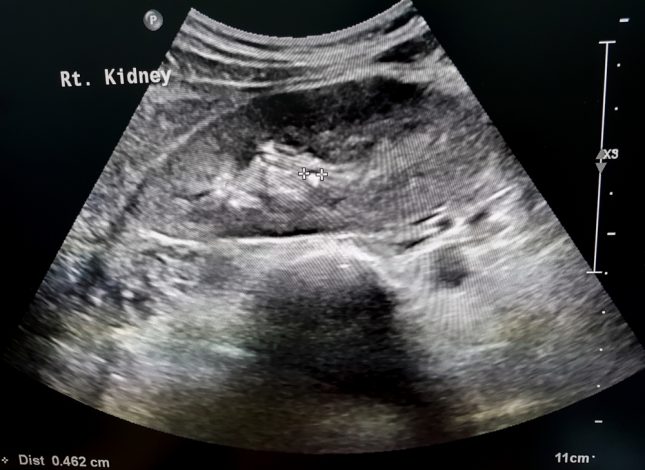

אבנים בכליות

אילו מטופלים נמצאים בסיכון מוגבר לאלח דם לאחר ריסוק אבני כליה מלעורי?